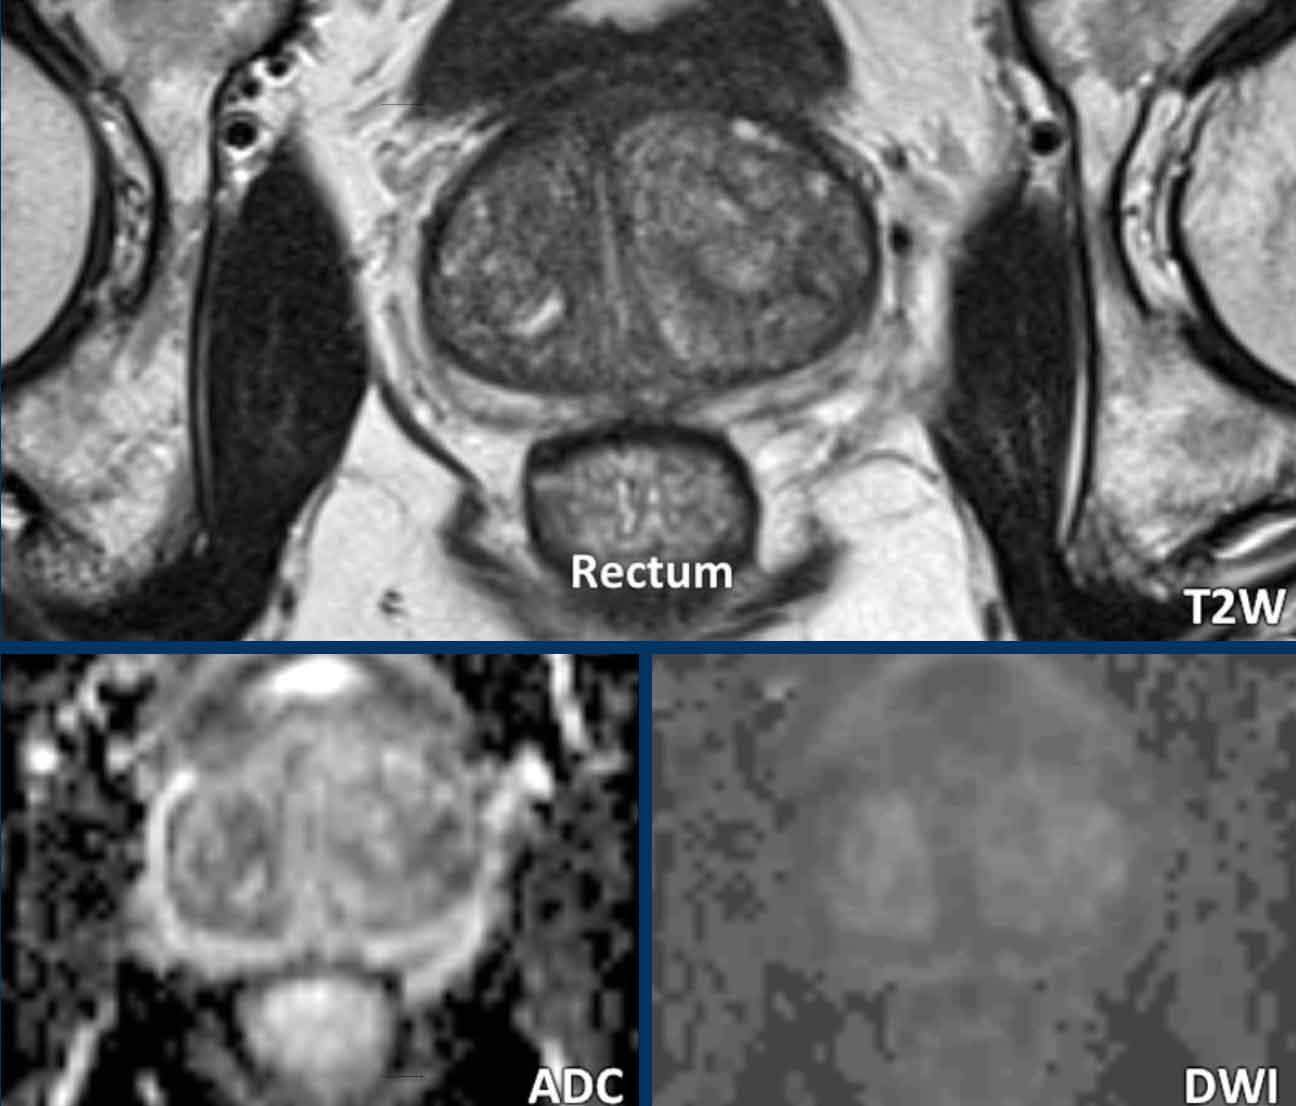

Thuốc giảm co thắt

Đây là ví dụ về một bệnh nhân đã được thụt tháo chuẩn bị tối thiểu vài giờ trước khi chụp.

Kết quả là trực tràng được làm sạch hoàn toàn. Mặc dù thụt tháo có thể gây nhu động trực tràng, nhưng không quan sát thấy xảo ảnh nào ở bệnh nhân này.